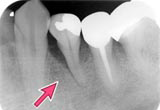

| 治療前 | 半年後 | 2年後 | ||

![]() |